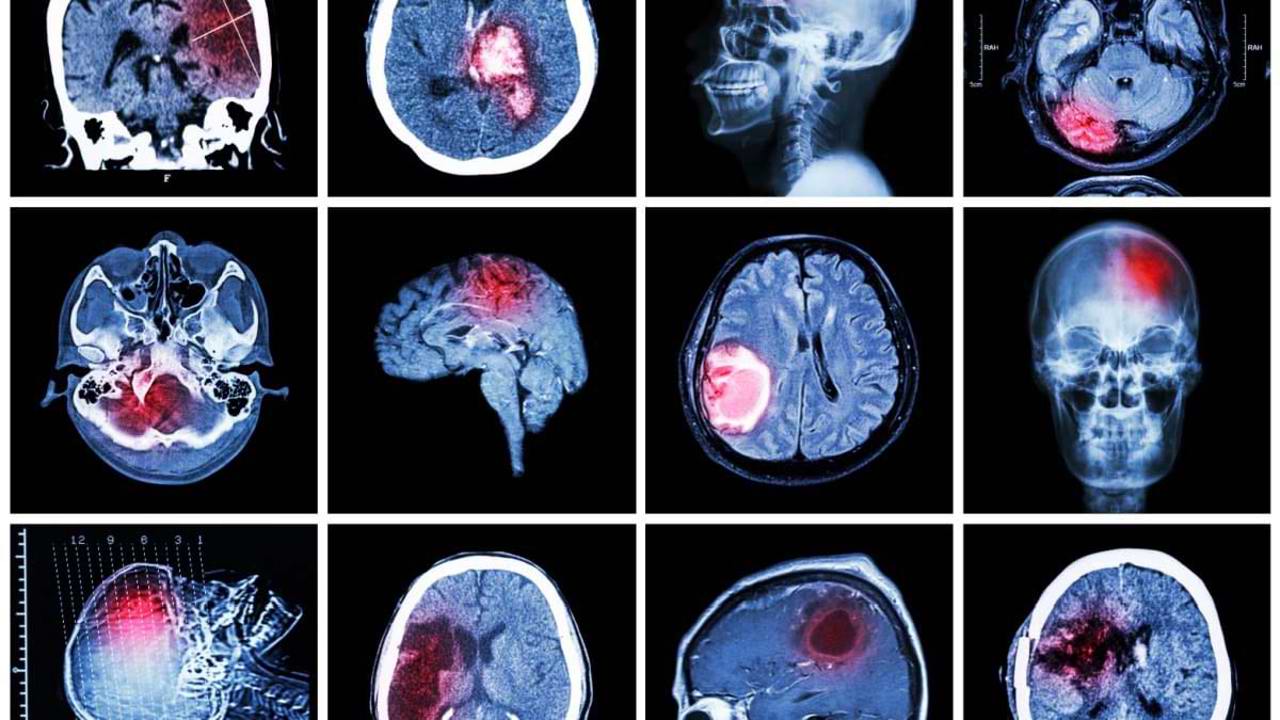

The educational project "Fast Heroes" will be launched in Chisinau, aiming to teach children how to recognize the signs of a stroke and how to respond appropriately to save lives. This initiative, carried out by the Center for Health Strategies and Policies (CSPS), involves primary school students and teachers in raising awareness about the dangers of stroke.

“Our mission is to raise awareness about the symptoms of stroke and the necessity for immediate action. The project involves teachers, who will play a key role in educating students about the signs of stroke,” the official emphasized.